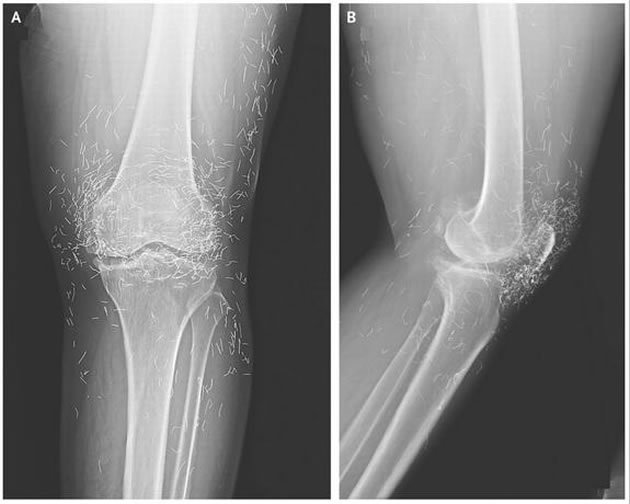

Os remédios não fizeram efeito, então os médicos pediram um raio-x, ela descobriu que não tinha doença ou lesão alguma, mas sim, pequenos pedaços de ouro presos em sua cartilagem.

Os pequenos pedaços de ouro que estão alojados, devem-se ao tratamento de acupuntura. Em suas sessões, o especialistas deixavam pequenos pedaços da agulha para aumentar a eficácia do tratamento. Como o raio-x indiciou a presença de ouro na cartilagem, é suposto que as agulhas usadas eram feitas deste material.